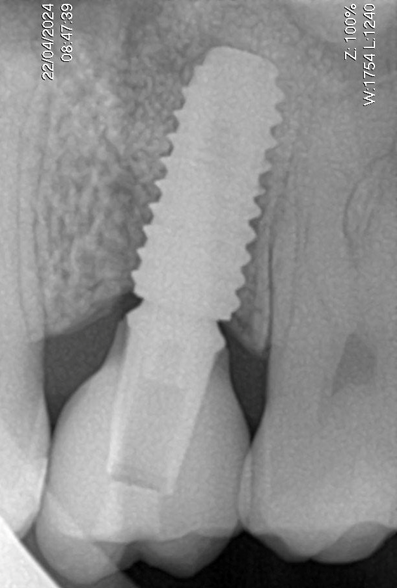

Enfim, um implante osseointegrável de 5.0 x 10 mm TS III (Osstem, Seul, República da Coréia) foi instalado (Figura 14). Após três meses foi feita a reabertura com enxerto de tecido conjuntivo do palato na vestibular e instalação de um cicatrizador (Figura 15). Um mês depois, um provisório foi instalado para promover o correto perfil de emergência gengival (Figura 16) e, então, foi utilizado um corpo de escaneamento (Osstem, Seul, República da Coréia), conforme Figura 16, para a realização do escaneamento para a moldagem digital. Uma coroa em dissilicato de lítio sobre pilar de titânio “Rigid” (Osstem, Seul, República da Coréia) foi confeccionada e parafusada sobre o implante com torque de 30 Ncm (Figura 17). Uma radiografia periapical final sugere a osseointegração do implante, a estabilidade do enxerto ósseo na região do seio maxilar e a perfeita adaptação protética após 12 meses (Figura 18).